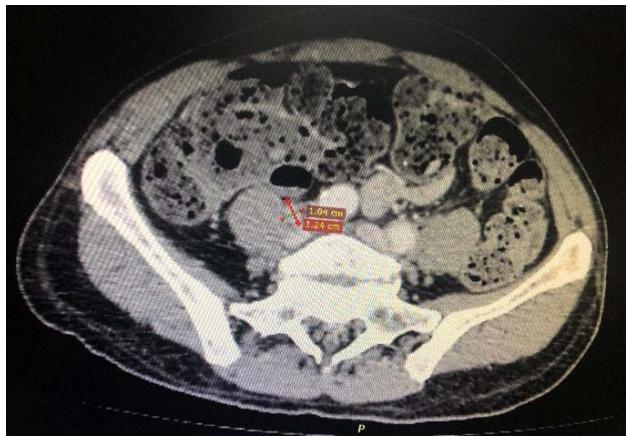

Computed tomography of the chest showed the presence of confluent lymphadenomegaly in the right axillary chain, forming a mass with a center of necrotic, measuring approximately $56 \times 40 \mathrm{~mm}$ in their largest diameters. Other non-confluent lymph nodes of increased size were observed in the ipsilateral axillary chain, left axillary chain and retroperitoneum. Abdominal CT scans showed prominent lymph nodes in the common iliac chain and bilateral inguinal nodes.

C Fig. 3: (A) CT scan of the right axillary region showing confluent lymph nodes forming a mass with a necrotic center measuring approximately $56 \times 40 \mathrm{~mm}$ in its largest diameters; (B and C) CT scan showing lymphadenopathy in chains in the right inguinal region and the right common iliac region respectively.